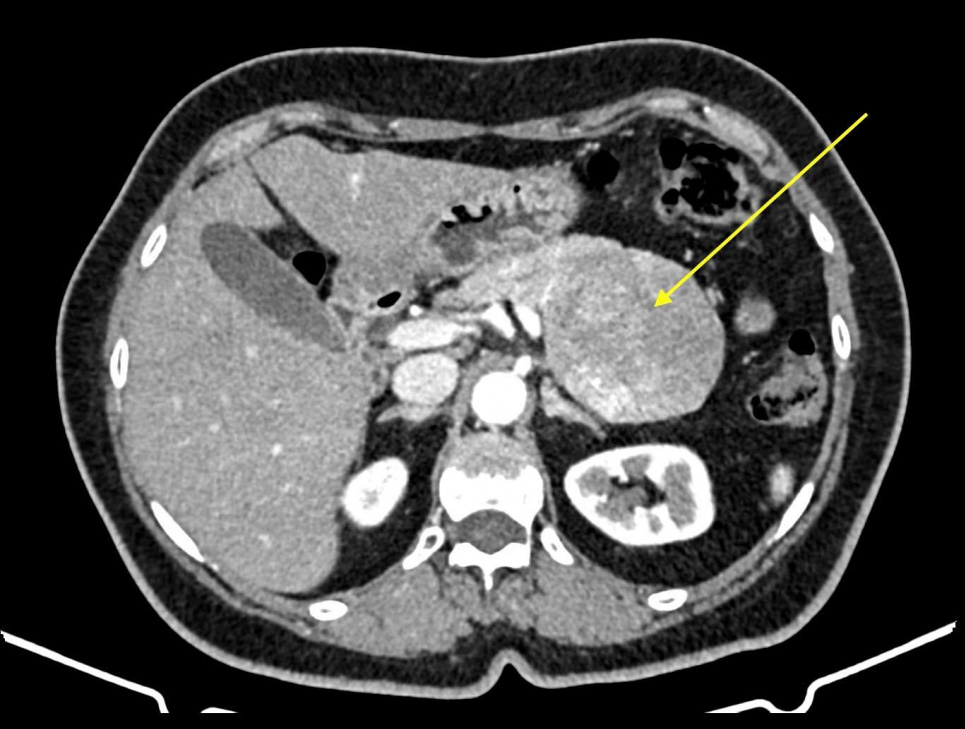

У Міській клінічній лікарні №1 м. Одеси успішно проведено складну малоінвазивну операцію з видалення пухлини підшлункової залози. Про це йдеться на Фейсбук сторінці головного лікаря “Комунальна установа “Міська клінічна лікарня №1” Євгена Григор`єва.

Хірургія пухлин підшлункової залози – один з найскладніших напрямів абдомінальної хірургії. Подібні операції зазвичай виконуються лише у закладах охорони здоров’я обласного рівня та науково-дослідницьких інститутах.

Пухлину було успішно видалено через мініатюрні розрізи/проколи, що мінімізує травматичність і пришвидшує одужання пацієнта.